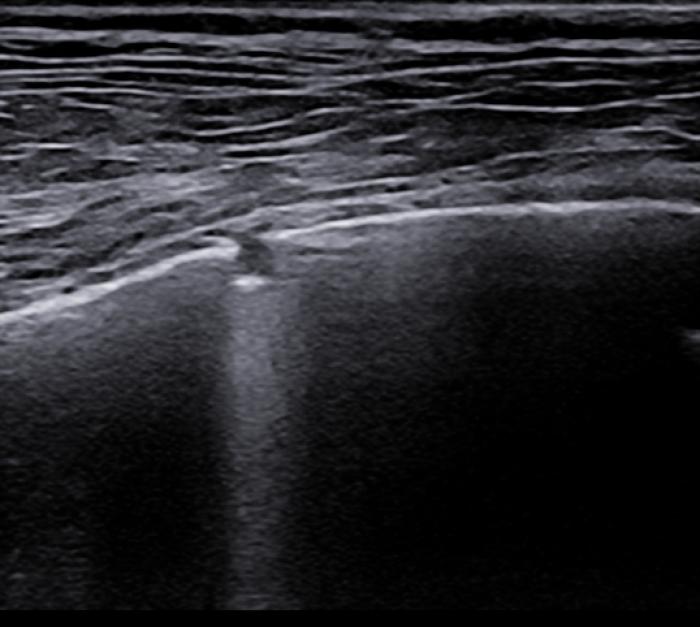

Signo de cuña

Se trata de una consolidación de aspecto triangular o trapezoidal cuya base se encuentra en la LP. Los bordes son más regulares que en el caso del signo de fragmentación, no presentan broncogramas aéreos y si es factible utilizar el Doppler veremos ausencia de flujo en el foco afectado. Comúnmente pueden ir asociados a efusión pleural y si el cuadro respiratorio es agudo, la causa más frecuente es el tromboembolismo pulmonar.

Existe cierta controversia con respecto a si en perros y gatos este signo se describe con aspecto triangular como ocurre en los humanos, puesto que anatómicamente hay diferencias con respecto a la sección menos triangular que describe la vasculatura y por tanto quizá sea más correcto hablar de un aspecto trapezoidal del área consolidada (como se visualiza en la figura 15.3) que puramente triangular (Figura 15A-D).